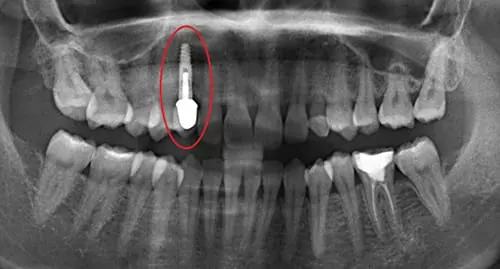

植牙術後全口環頸式X光片

- 進行植牙第一階段人工牙根植入。

- 待骨整合後,進行植牙第二階段,癒合基座置入,以利牙齦塑型。

- 待牙齦成型後,進行植牙第三階段牙冠製作。